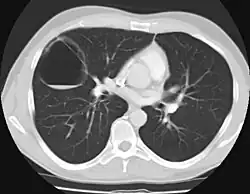

- Typ III: (<10 %) mikroskopisch kleine Zysten. In der Bildgebung zeigt sich eine solide Masse.[2]

Nach der Geburt: Röntgen der Lunge, CT, ggf. Bronchoskopie, NMR